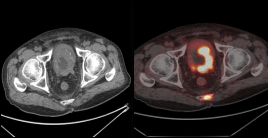

前列腺癌治疗后复发:18F-PSMA PET/CT显像示前列腺癌去势治疗术后复发并骶尾椎骨转移瘤。